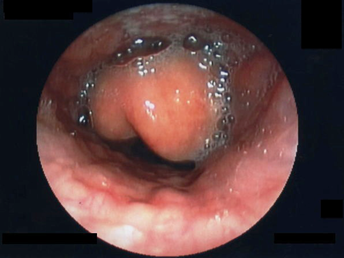

Diagnosis of peritonsillar abscess typically is clinical and involves an examination of the posterior oropharynx, demonstrating a deviated uvula with significant unilateral peritonsillar edema. (See Figure 1.) Symmetric bilateral swelling of the peritonsillar areas can be seen in tonsillitis and typically is not seen in peritonsillar abscess. Trismus is common in patients with peritonsillar abscess and is related to the inflammation and spasm of the internal pterygoid muscle. Examination may be challenging in patients with significant trismus.

Figure 1. Peritonsillar Abscess |

Courtesy of James Heilman, MD. PeritonsilarAbsess.jpg. https://commons.wikimedia.org/wiki/File:PeritonsilarAbsess.jpg CC BY-SA 3.0 |